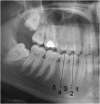

Objectives: To determine the radiographic position and reliability of assessing mental foramen (MF) position in relation to premolar crowns in an 18- to 30-year-old UK-based population.

Methods: Following ethical approval and a power calculation, the position of the MF was recorded in relation to premolar crowns and apices in 100 dental panoramic tomographs. Positions were assessed by three senior clinicians independently, then by consensus. Data were analysed using descriptive statistics, χ(2) and Fleiss' and Cohen's kappa.

Results: Reliability data showed only fair to moderate agreement on independent scoring. Substantial to almost perfect agreement was achieved by consensus, demonstrating the most common position for the MF to be between the first and second premolar teeth when using both premolar crowns (51%) and apices (76%) as reference points. There was a significant difference in the position of the foramen between the left and right sides (p < 0.05), with only 62% of cases showing symmetry.

Conclusions: The most common position for the MF is between the first and second premolar teeth; however, anatomical variation is seen. Use of pre-operative radiographs to relate the position of the MF to premolar crowns may not be reliable.